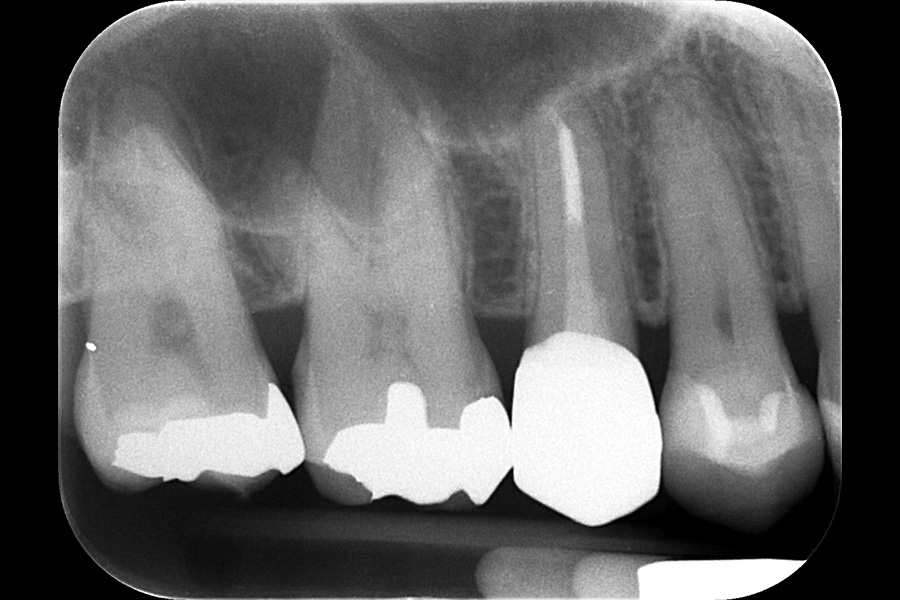

治療前

| 主訴 | 右上の奥歯の歯茎が腫れている |

| 治療内容 | 上顎右側第二小臼歯 再根管治療 |

| 治療に伴うリスク | 残存歯質が歯肉より深い場合は歯の保存が困難、経過によっては外科的歯内療法が必要 |